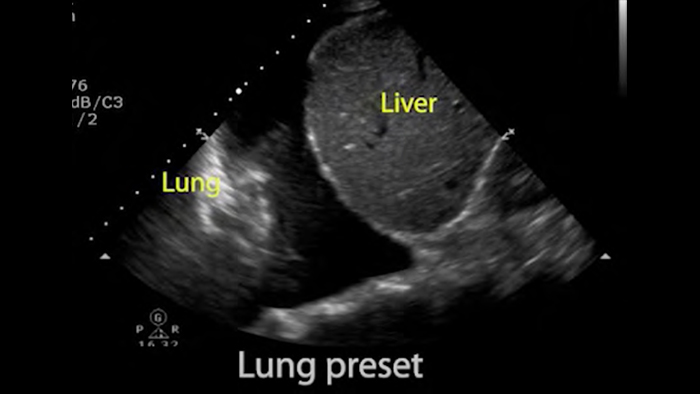

Use Lumify for airway and pulmonary assessment

Lumify POCUS solutions can help you detect the endotracheal tube within the trachea, assist in emergent cricothyrotomy procedures, diagnose pleural effusion and interstitial alveolar diseases.

Pulmonary assessment